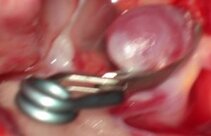

Aneurysma: Die mikrochirurgische Behandlung mittels Clipping

Beim Clipping handelt es sich um eine offene mikrochirurgische Operation, wobei in Narkose eine Schädeleröffnung, Kraniotomie genannt, vorgenommen wird. Unter dem Operationsmikroskop wir das Aneurysma aufgesucht und mit einem Titanclip von dem Trägergefäß isoliert. Der Schädelknochen wird wieder eingesetzt, die Wunde wird verschlossen.

Vorteil des Clipping: Das Ausschalten des Aneurysmas verläuft unter Sicht, eine Kontroll-Angiographie ist nur selten nötig.

Nachteil des Clipping: Die vorherige Eröffnung des Schädels.